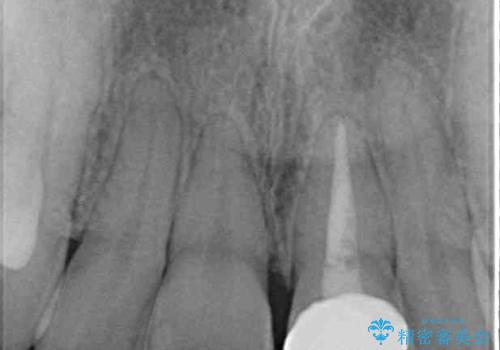

- 前歯のクロスバイトと神経を取り除いた後に変色してしまった前歯を気にして来院された患者様です。

ワイヤー矯正により矯正治療を行った後に、前歯の補綴治療を行うこととしました。

変色してしまった前歯は、反対側の歯と比べて歯肉が覆い被さっていたため、骨整形を含めた歯周外科処置を行い、歯肉ラインを整えることとしました。